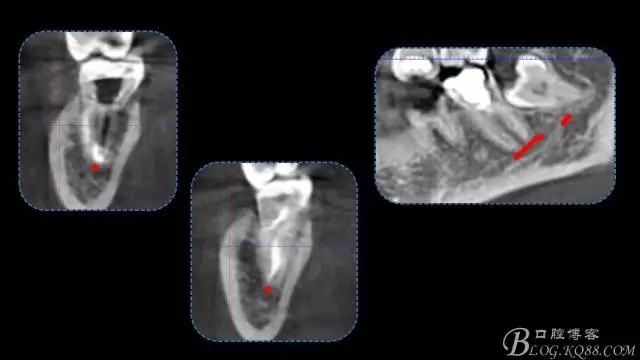

行走在神經(jīng)管上的根管治療